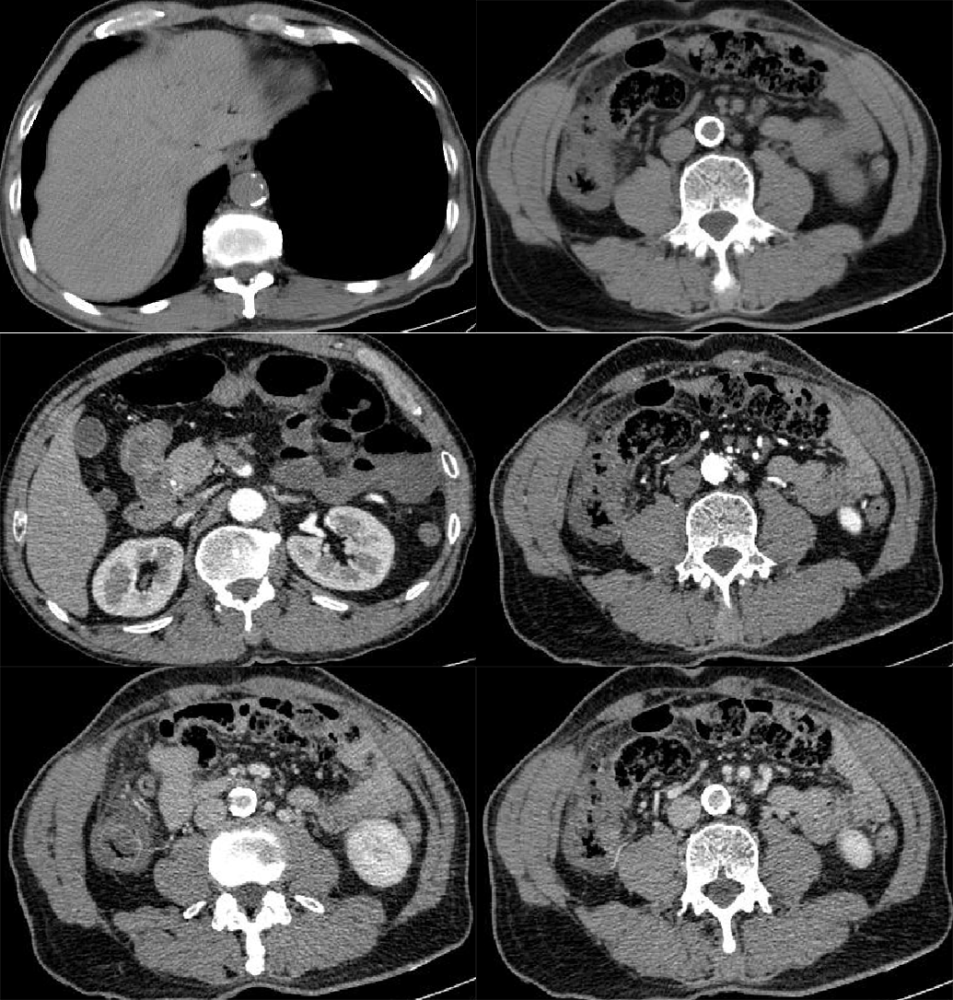

【病例】肠系膜上动脉栓塞2例ct影像

图片尺寸962x768